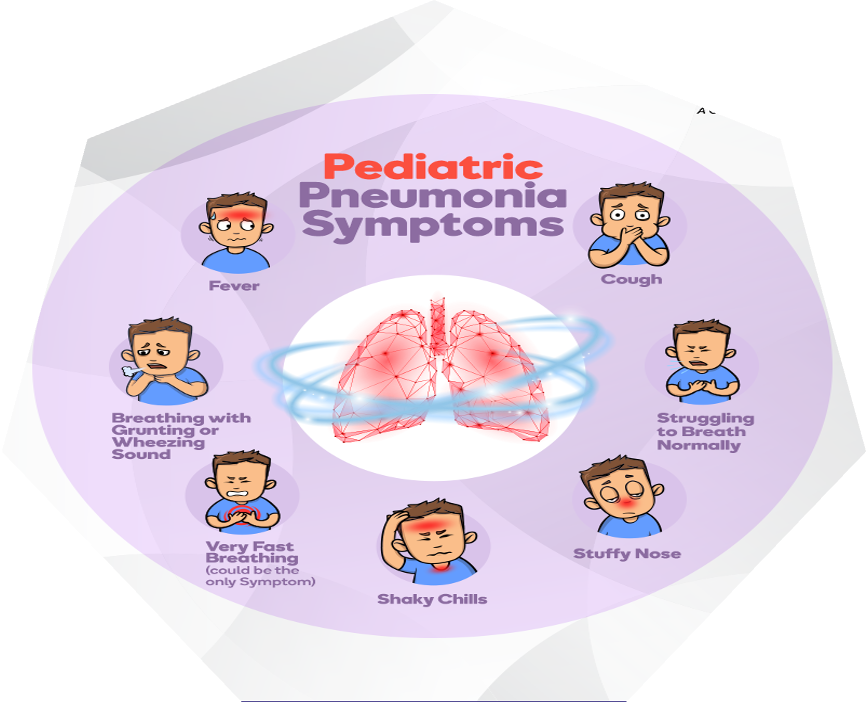

CLINICAL PICTURE

Presenting features vary with age, infectious agent, and severity or stage of the illness.

- Fever, cough (productive or non-productive), and difficulty breathing are common presenting symptoms, often preceded by signs of a minor upper respiratory tract infection.

- Chest or stomach pain.

- Decrease in appetite.

- Chills.

- Breathing fast or hard.

- Vomiting.

- Headache.

- Not feeling well.